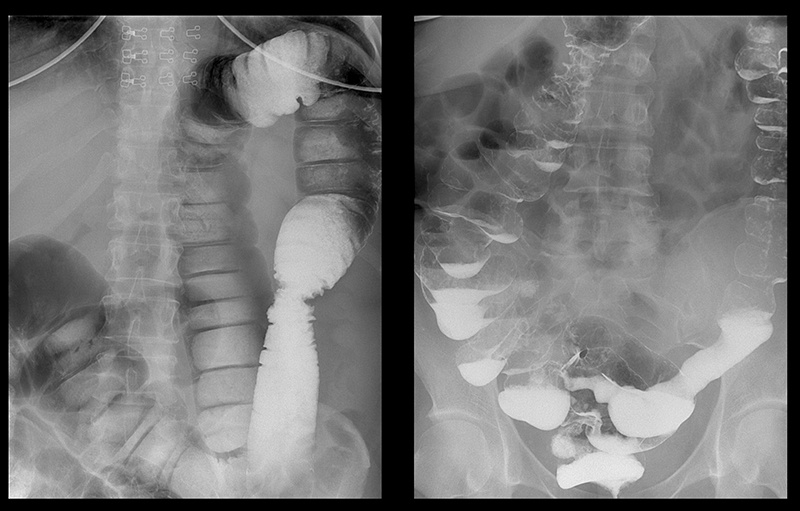

‘’Стадії раку прямої кишки які формуються протягом 1-2 років’’